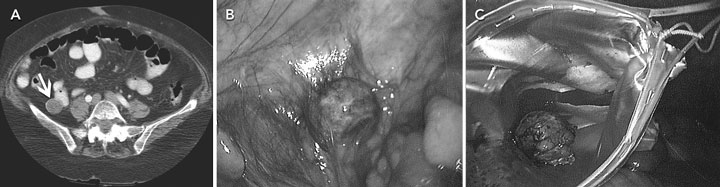

Laboratory investigations showed a serum lipase concentration of 393 U/L (reference range, 114–286 U/L) with normal white blood cell count. Abdominal computed tomography revealed a 2.8 × 2.4 cm mass in the right lower quadrant, with a calcific rim and foci of calcium within the lesion (Figure, A). The mass appeared to be outside the small bowel, suggesting a mucocele or mucoid tumour. Laparoscopy revealed a 2.5 cm solid mass containing a gallstone (Figure, B and C). The drainage from the umbilicus continued after surgery and was apparently unrelated to the spilled gallstone.